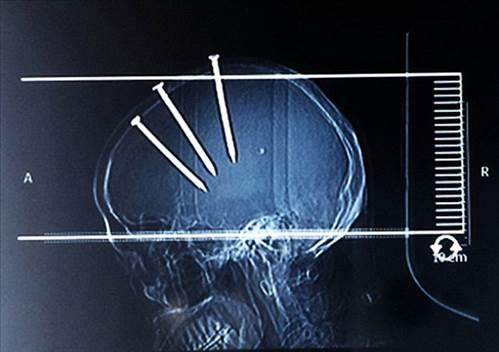

5. Çinli bir adam hastaneye getirildiğinde bu görüntüsü ile herkesi şaşırttı..

Çinli bir adam hastaneye getirildiğinde bu görüntüsü ile herkesi şaşırttı..

6. Çivilerin başları açıkça dışarıdan bile görünürken doktorlar Çinli adamın röntgenini çekti ve 3 koca çivi ile karşılaştı...

Çivilerin başları açıkça dışarıdan bile görünürken doktorlar Çinli adamın röntgenini çekti ve 3 koca çivi ile karşılaştı...

7. Hemen ameliyata alınan adamın başındaki çiviler teker teker çıkarıldı...

Hemen ameliyata alınan adamın başındaki çiviler teker teker çıkarıldı...

8. Çivilerin hepsi çıkarıldıktan sonra bir süre gözetim altında tutulan adamın sağlığı normale dönünce taburcu edildi...

Çivilerin hepsi çıkarıldıktan sonra bir süre gözetim altında tutulan adamın sağlığı normale dönünce taburcu edildi...

9. Yapılan araştırmada Çinli adamın evini tamir ederken çivi tabancası ile yaralandığı ortaya çıktı...

Yapılan araştırmada Çinli adamın evini tamir ederken çivi tabancası ile yaralandığı ortaya çıktı...

10. Başına çakılan çivilerden 2 gün sonra haberdar olan adamın şimdi sağlığı gayet yerinde...

Başına çakılan çivilerden 2 gün sonra haberdar olan adamın şimdi sağlığı gayet yerinde...